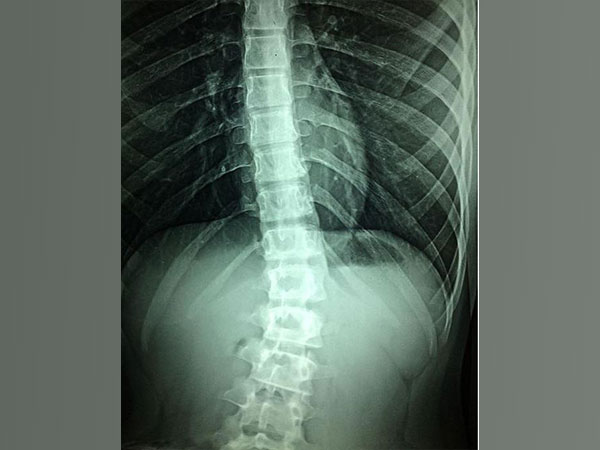

Washington [US], August 3 (ANI): According to a study, children and teenagers with scoliosis who undergo spinal fusion can still be given an acceptable amount of pain medication while using fewer opioids.

"Spinal fusion is arguably one of the most painful procedures we perform in pediatric orthopaedics, but our findings show we can provide excellent pain control by employing multimodal pain management techniques and preoperative education," said G. Ying Li, M.D., senior author of the study and orthopaedic surgeon at U-M Health C.